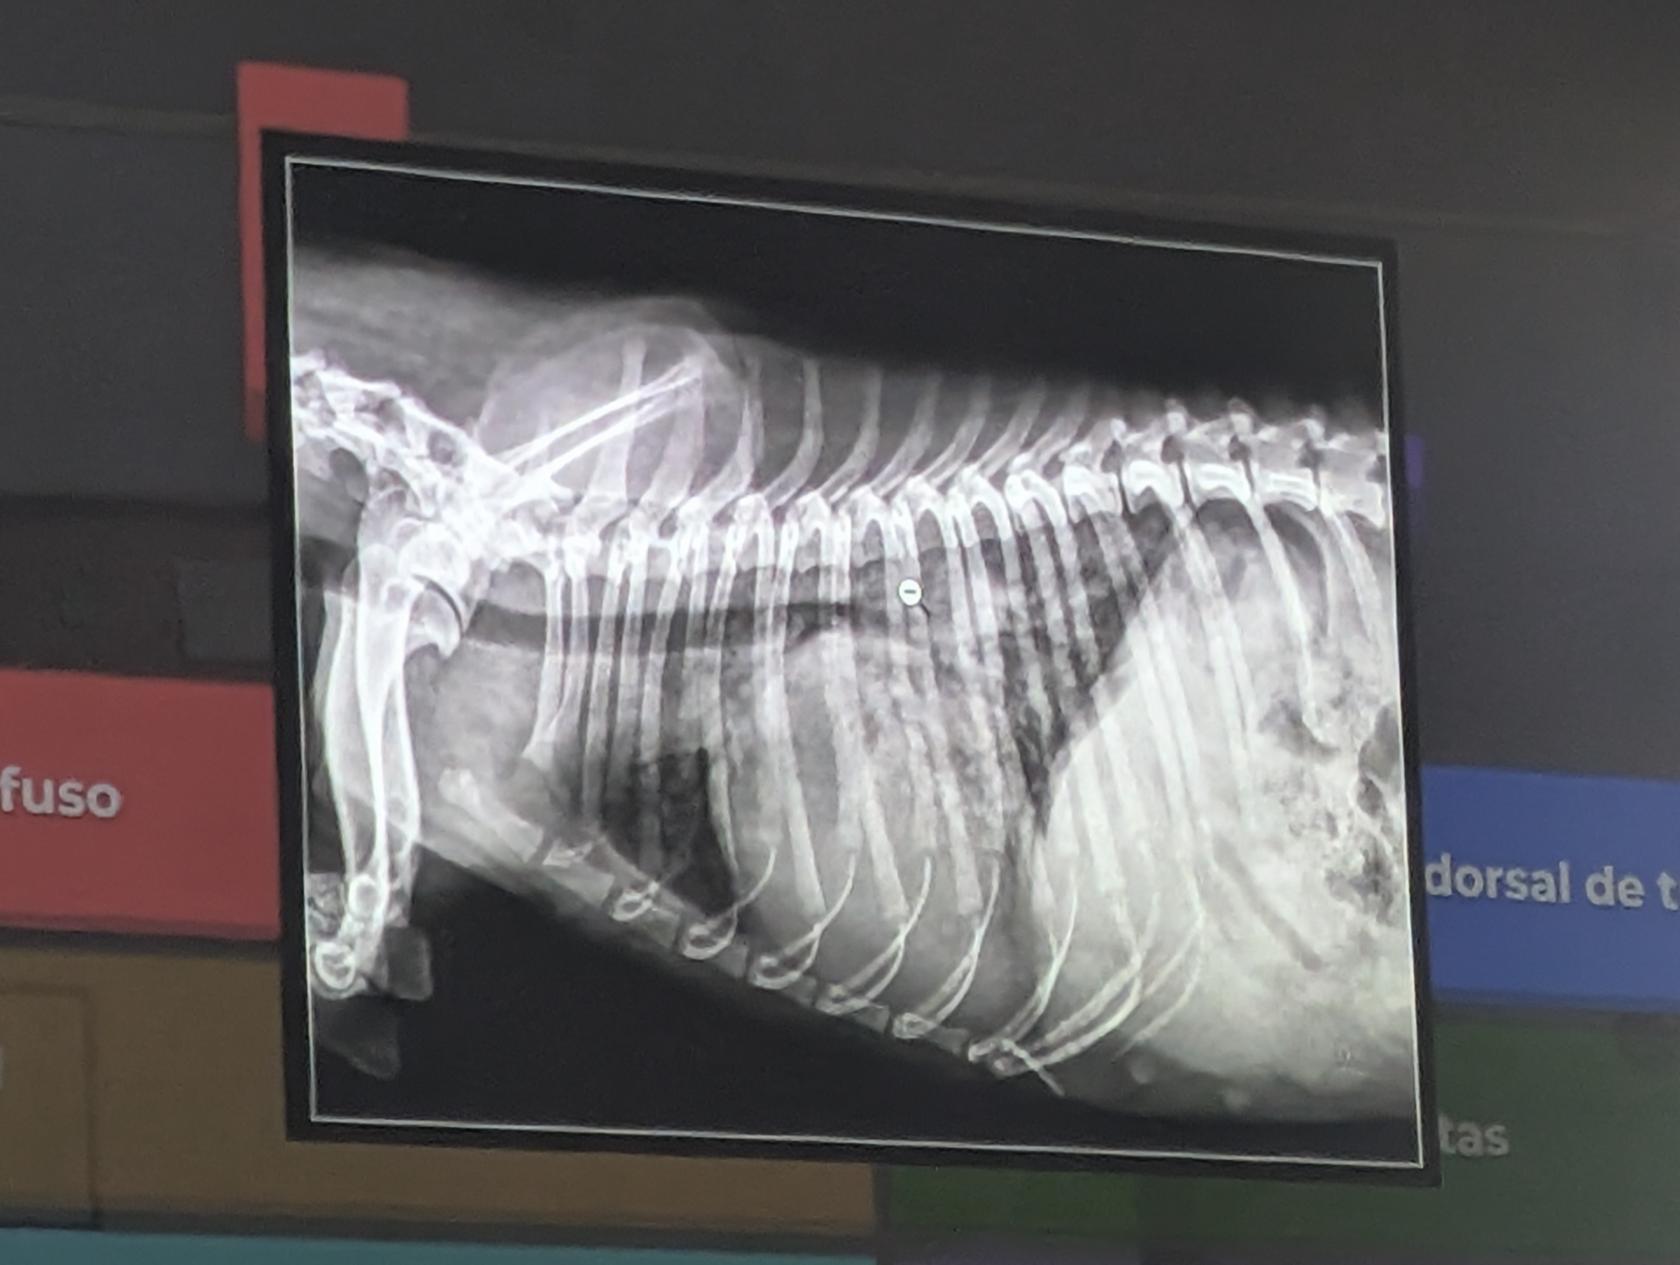

- Se trata de un abdomen de perro

- Dilatacion gastrica

- Cuerpo extraño en el estomago (Linea radiopaca en el piloro)

- Eje gastrico alterado.

- Cumple dos criterios de hepatomegalia. (El higado ocupa mas parte, avanzando mas costillas, desplaza al estomago)